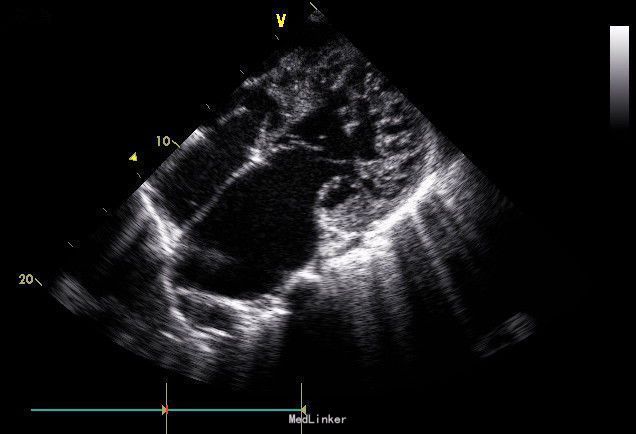

入院后予以肺表面活性物质、机械通气、对症支持治疗。第三天出现患儿出现全身皮肤花纹样改变,血压下降。予静脉给予氢化可的松3mg/kg,q12h。复查心电图:窦性心动过速,异常Q波,偶发室性早搏,右心室肥厚,ST-T改变。心脏彩超:左心扩张,左室基底段后侧壁心肌发育欠佳,明显变薄,厚约1.6mm,左室中下段心肌内可见弥漫分布的肌窦结构,其中下壁心尖段致密心肌厚约1mm,非致密心肌厚约3.1mm,后内侧乳头肌根部呈网格状改变,右心未见增大。确诊为:左室致密化不全性心肌病。家属放弃治疗。

讨论:心肌致密化不全性心肌病是一种罕见的心脏疾病,其临床表现多样,以心力衰竭、心律失常、血栓栓塞为典型的三大症状,临床上应注意与心内膜弹力纤维增生症、扩张性心肌病等鉴别,超声心动图是诊断心肌致密化不全性心肌病简单又可靠方法。